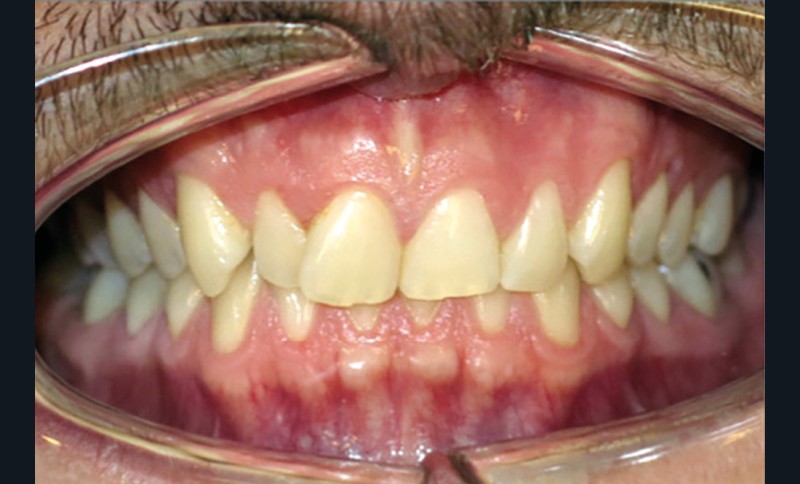

Discussion (fig. 4 à 7)

Le traitement a duré vingt-quatre mois. Le décalage de classe II complet à droite a nécessité une mécanique importante impliquant une bonne coopération du patient ainsi qu’un contrôle rigoureux des effets parasites. Les documents de fin de traitement nous montrent une normalisation des rapports incisifs. La correction de la classe II a entraîné une vestibulo-version de l’incisive mandibulaire qui reste néanmoins acceptable, et qui participe à la fermeture de l’angle interincisif, recherchée dans le traitement des classes II division 2. Les fonctions ont été rééduquées. Sur le plan esthétique, les améloplasties réalisées sur les bords libres de 12 à 22 ont permis d’effacer les séquelles de la supraclusion et participent à l’harmonisation du sourire.